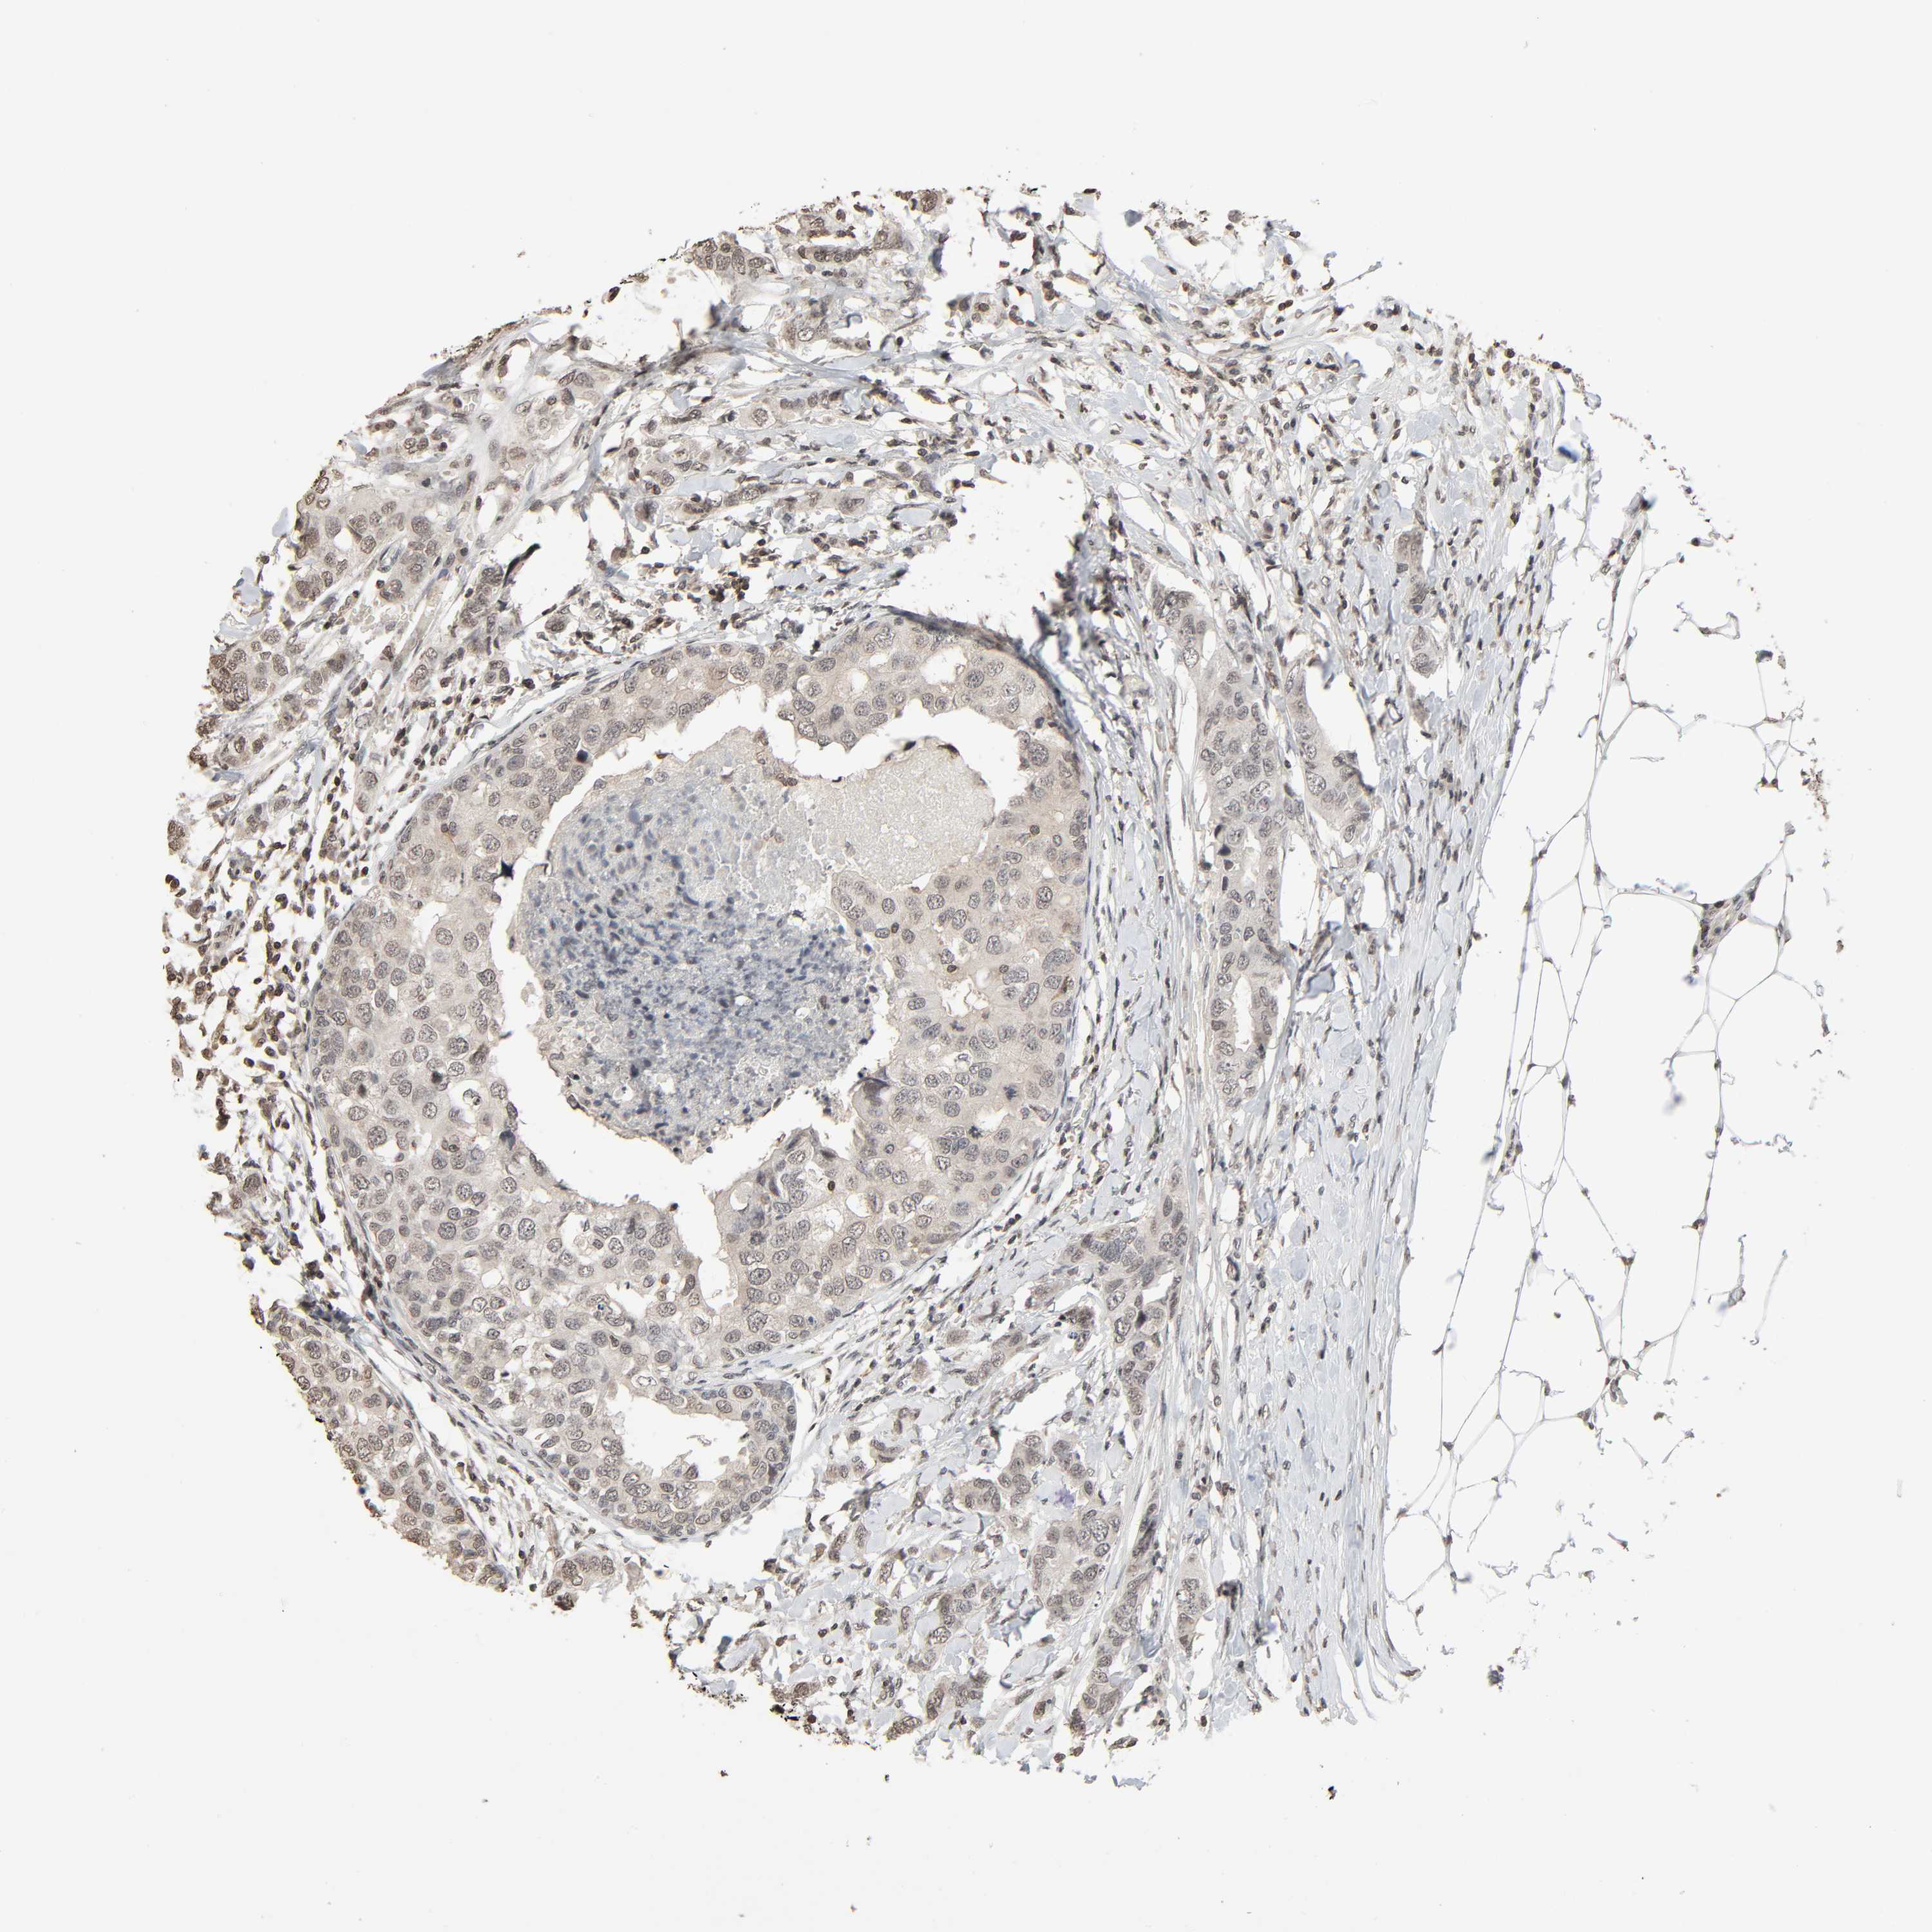

CANCER BREAST CANCER Show tissue menu

Breast cancer

Human cancer